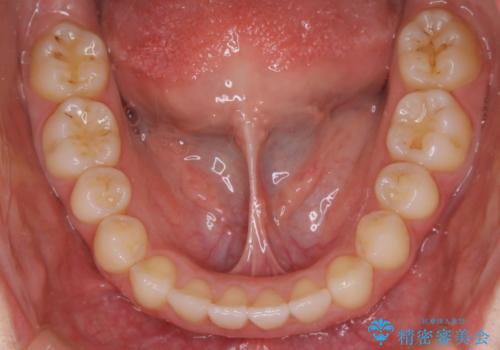

- 前から2番目の歯が捻じれていることが気になるとご相談にいらした方です。

インビザラインFULLで治療を行いました。

上の前から2番目の歯は、一般的に周囲の歯と比べて小さく、動きづらい歯であると言われています。前歯にゴムかけを行うことで理想的な位置まで歯を動かしてくることが出来ました。